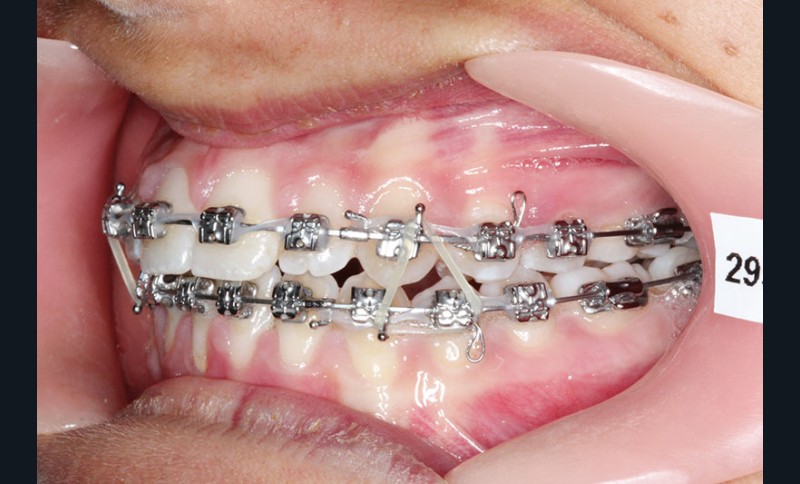

2e phase : mise en place du système multibague Carriere SLX (fig. 7 à 9)

Nous continuons le port des élastiques…